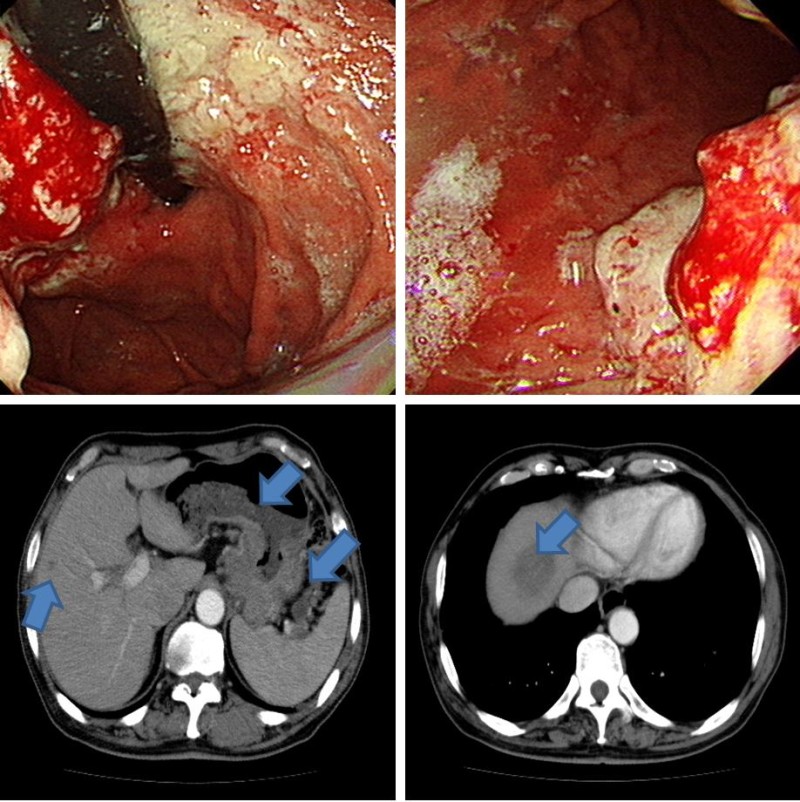

위암 생존율